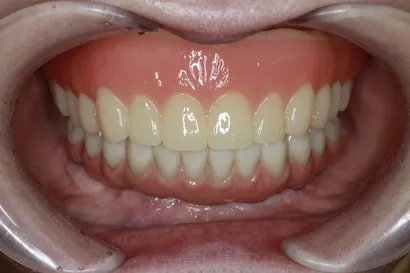

入れ歯からの全顎インプラント治療

50代 男性

執刀医 Dr.大杉 治療内容 重度の歯周病で、上下ともに顎の骨が大幅に痩せてしまった患者様です。総入れ歯も選択肢の一つでしたが、特に骨の吸収が激しい下顎では、安定せず「うまく噛めない・外れる」といった問題が予測されました。そのため下顎は、4本のインプラントで全ての歯を固定する「オールオン4」で、噛む機能を取り戻しました。

上顎:フルデンチャー(通常の粘膜を支えにした義歯)

下顎:ピンクポーセレンを用いたチタンフレーム入りのフルジルコニアインプラントブリッジ治療期間 1年3ヶ月 費用 上顎:75万 税抜

下顎:360万 税抜リスク 過去に歯周病と診断された方は、インプラントも歯周病(インプラント周囲炎)になるリスクが通常より高い傾向があります。そのため、治療後は特に注意が必要です。クリニックでの定期的なメンテナンスと、毎日の徹底したブラッシングを一緒に頑張り、インプラントを長持ちさせましょう。 -